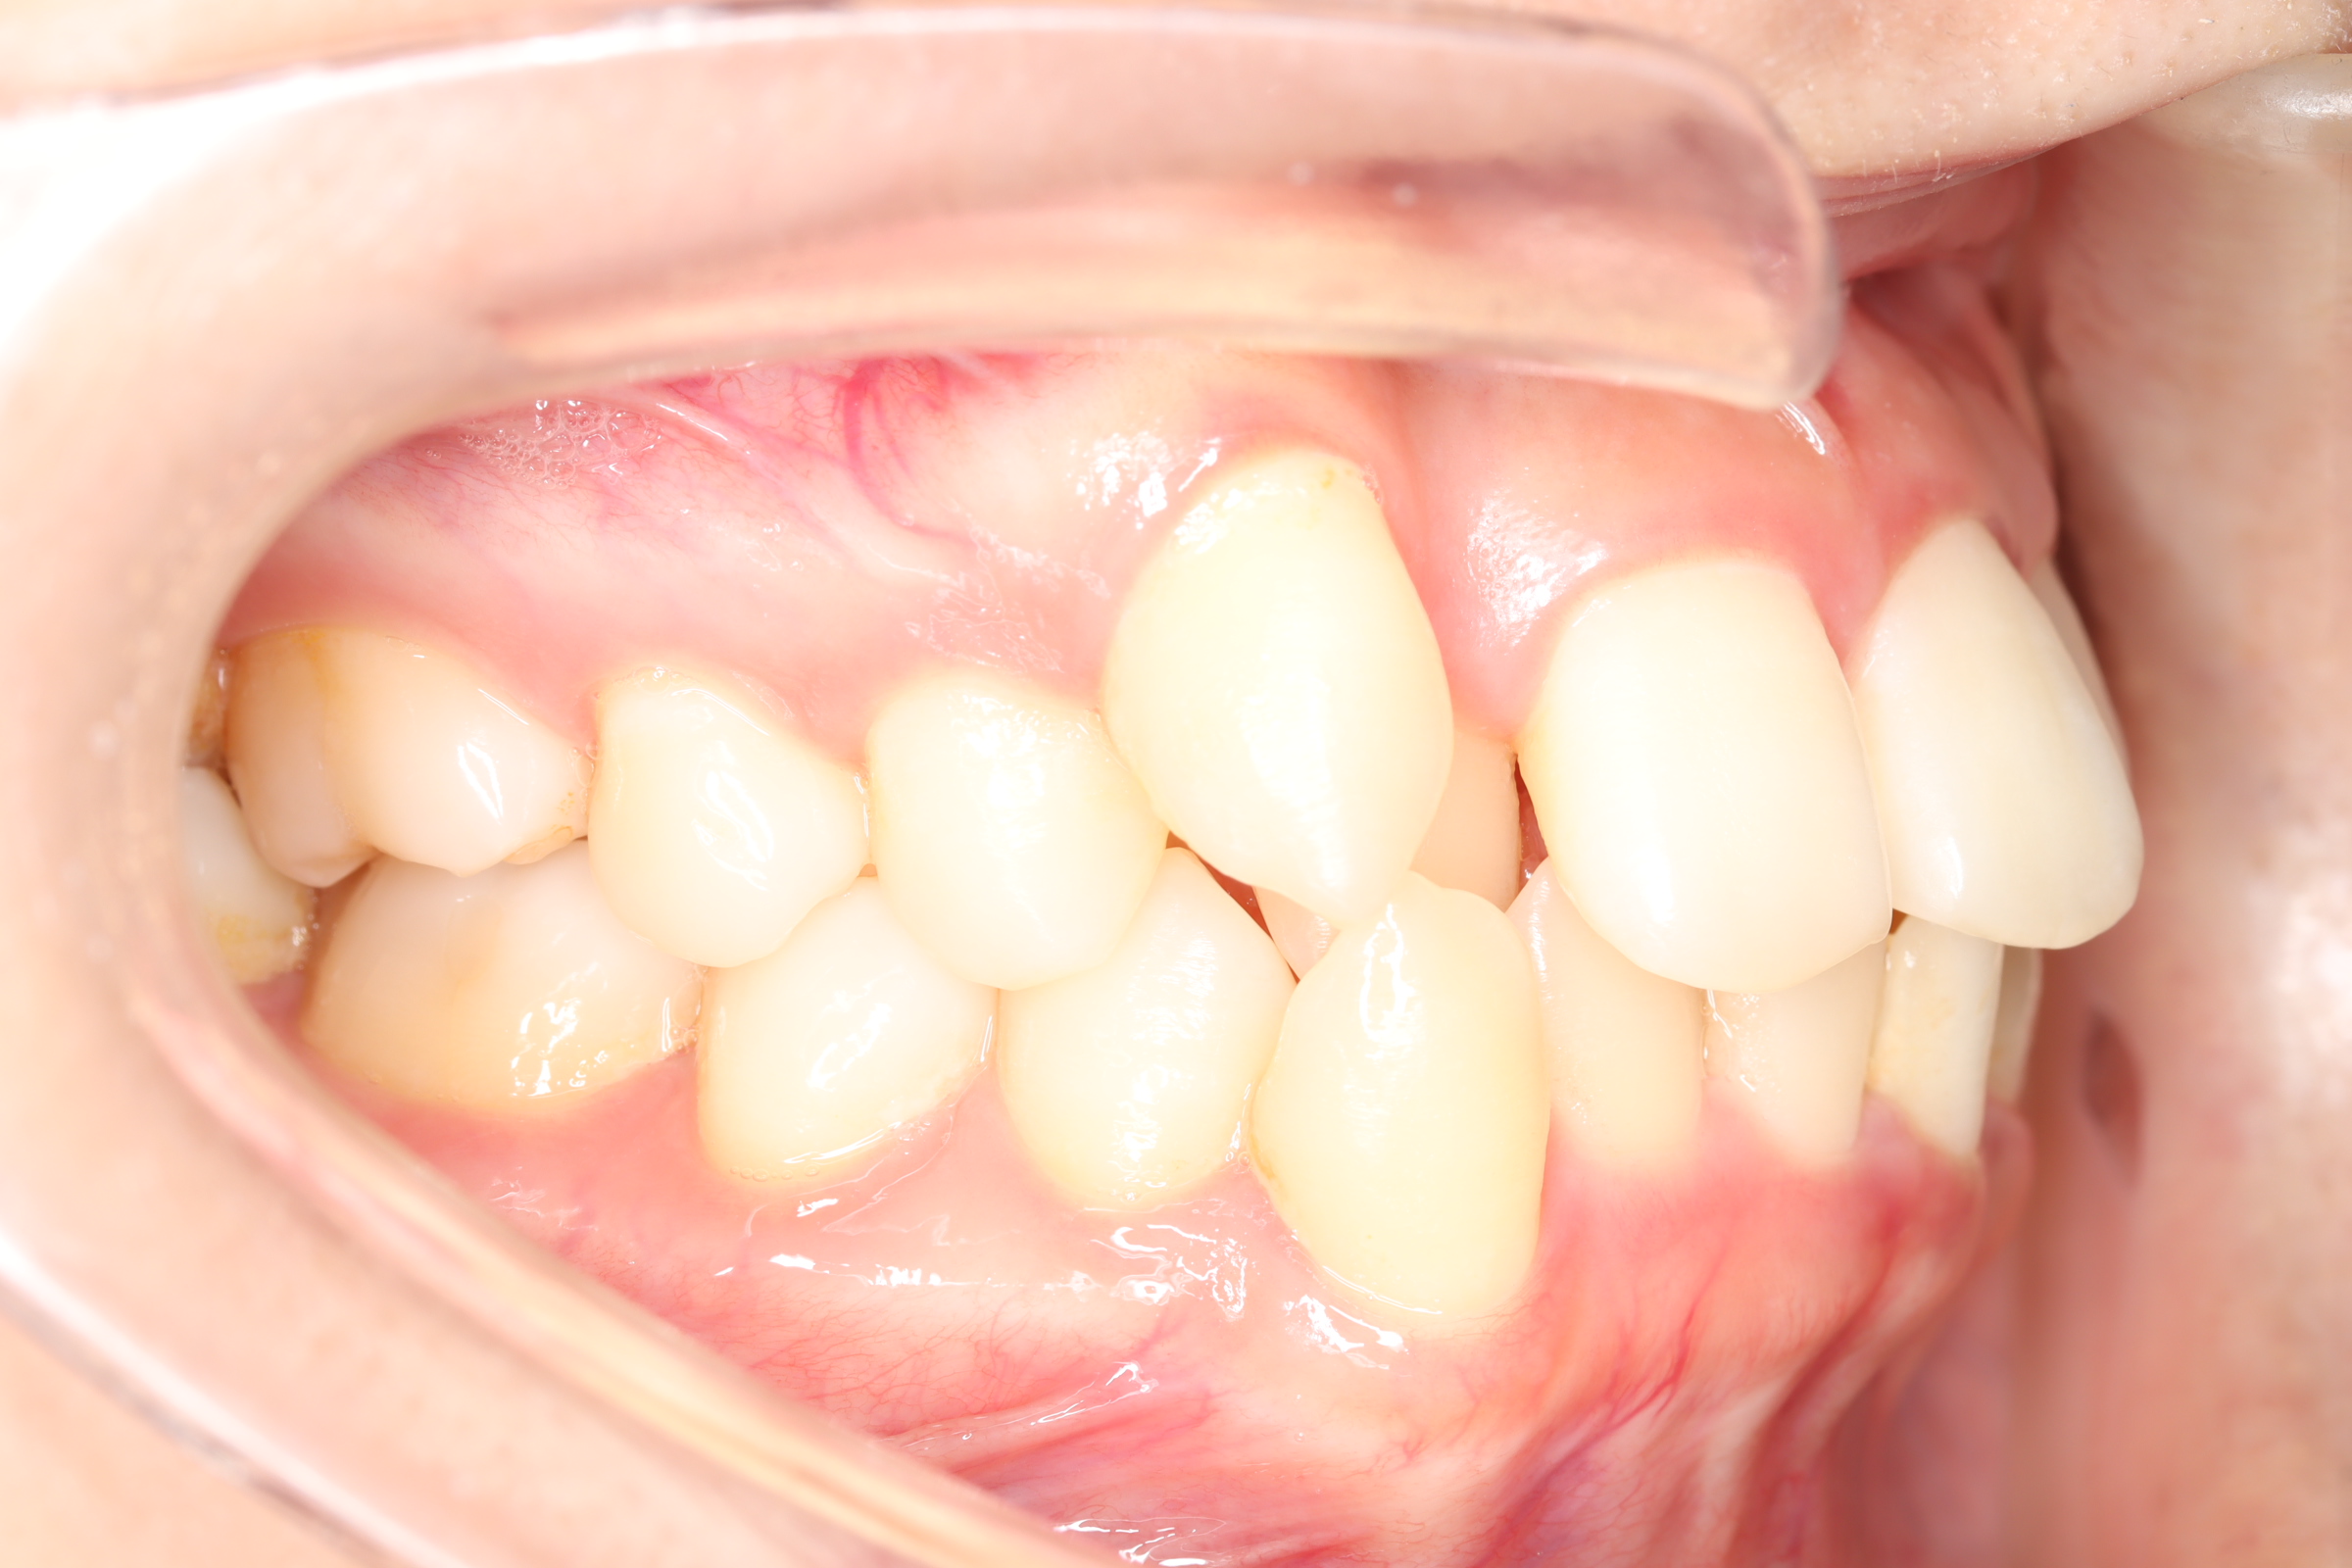

舌側(リンガル)矯正での叢生(ガチャ歯)の治療

口腔内の変化

| 治療前 | SNSなどで「ガチャ歯」と呼ばれている、見た目のがたつきを治したかった患者さんです。 骨格的な問題はありませんでしたが、上下の前歯が唇側傾斜しており、上下顎前突症で口元の突出感がありました。 |